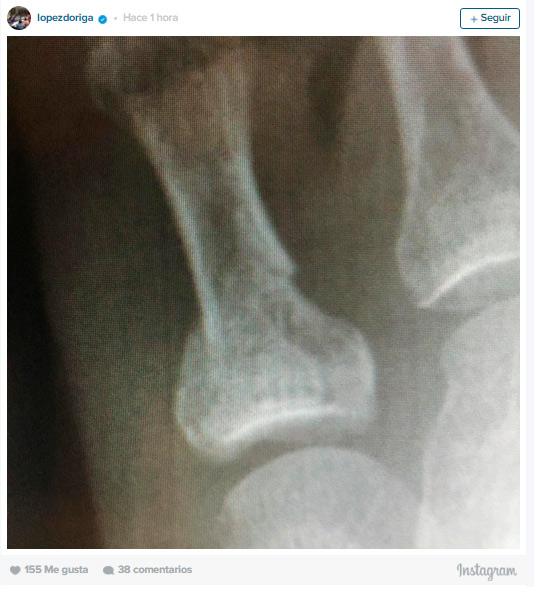

Joaquín López Dóriga compartió en sus redes sociales que había sufrido un pequeño accidente y se rompió un dedo del pie.

La noticia la dio a conocer con esta foto que muestra lo sucedido.

«¡Y qué me rompo el dedo chico del pie derecho! Se me atravesó la pata de una mesa y yo descalzo! ¿El motivo? Lo que están pensando…»